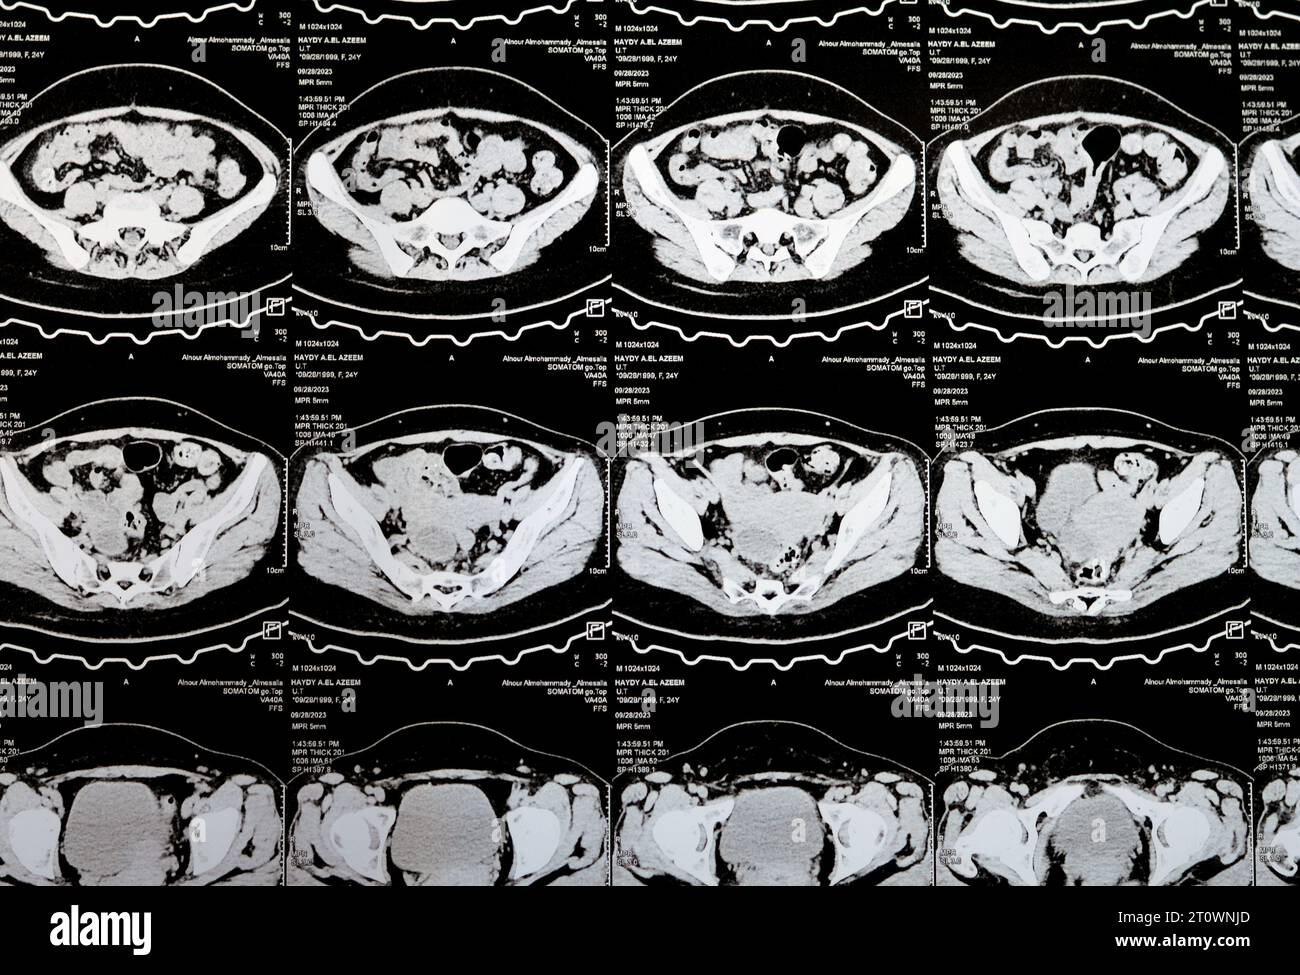

Le Caire, Égypte, octobre 3 2023 : le scanner multi-coupes de l'abdomen et du bassin montre un kyste de l'ovaire droit de 3 x 3 cm, une distension gazeuse colique, pas d'urine importante Banque D'Imageshttps://www.alamyimages.fr/image-license-details/?v=1https://www.alamyimages.fr/le-caire-egypte-octobre-3-2023-le-scanner-multi-coupes-de-l-abdomen-et-du-bassin-montre-un-kyste-de-l-ovaire-droit-de-3-x-3-cm-une-distension-gazeuse-colique-pas-d-urine-importante-image568526222.html

Le Caire, Égypte, octobre 3 2023 : le scanner multi-coupes de l'abdomen et du bassin montre un kyste de l'ovaire droit de 3 x 3 cm, une distension gazeuse colique, pas d'urine importante Banque D'Imageshttps://www.alamyimages.fr/image-license-details/?v=1https://www.alamyimages.fr/le-caire-egypte-octobre-3-2023-le-scanner-multi-coupes-de-l-abdomen-et-du-bassin-montre-un-kyste-de-l-ovaire-droit-de-3-x-3-cm-une-distension-gazeuse-colique-pas-d-urine-importante-image568526222.htmlRF2T0XGYX–Le Caire, Égypte, octobre 3 2023 : le scanner multi-coupes de l'abdomen et du bassin montre un kyste de l'ovaire droit de 3 x 3 cm, une distension gazeuse colique, pas d'urine importante

Le Caire, Égypte, octobre 3 2023 : le scanner multi-coupes de l'abdomen et du bassin montre un kyste de l'ovaire droit de 3 x 3 cm, une distension gazeuse colique, pas d'urine importante Banque D'Imageshttps://www.alamyimages.fr/image-license-details/?v=1https://www.alamyimages.fr/le-caire-egypte-octobre-3-2023-le-scanner-multi-coupes-de-l-abdomen-et-du-bassin-montre-un-kyste-de-l-ovaire-droit-de-3-x-3-cm-une-distension-gazeuse-colique-pas-d-urine-importante-image568533363.html

Le Caire, Égypte, octobre 3 2023 : le scanner multi-coupes de l'abdomen et du bassin montre un kyste de l'ovaire droit de 3 x 3 cm, une distension gazeuse colique, pas d'urine importante Banque D'Imageshttps://www.alamyimages.fr/image-license-details/?v=1https://www.alamyimages.fr/le-caire-egypte-octobre-3-2023-le-scanner-multi-coupes-de-l-abdomen-et-du-bassin-montre-un-kyste-de-l-ovaire-droit-de-3-x-3-cm-une-distension-gazeuse-colique-pas-d-urine-importante-image568533363.htmlRF2T0XX2Y–Le Caire, Égypte, octobre 3 2023 : le scanner multi-coupes de l'abdomen et du bassin montre un kyste de l'ovaire droit de 3 x 3 cm, une distension gazeuse colique, pas d'urine importante

Le Caire, Égypte, octobre 3 2023 : le scanner multi-coupes de l'abdomen et du bassin montre un kyste de l'ovaire droit de 3 x 3 cm, une distension gazeuse colique, pas d'urine importante Banque D'Imageshttps://www.alamyimages.fr/image-license-details/?v=1https://www.alamyimages.fr/le-caire-egypte-octobre-3-2023-le-scanner-multi-coupes-de-l-abdomen-et-du-bassin-montre-un-kyste-de-l-ovaire-droit-de-3-x-3-cm-une-distension-gazeuse-colique-pas-d-urine-importante-image568532396.html

Le Caire, Égypte, octobre 3 2023 : le scanner multi-coupes de l'abdomen et du bassin montre un kyste de l'ovaire droit de 3 x 3 cm, une distension gazeuse colique, pas d'urine importante Banque D'Imageshttps://www.alamyimages.fr/image-license-details/?v=1https://www.alamyimages.fr/le-caire-egypte-octobre-3-2023-le-scanner-multi-coupes-de-l-abdomen-et-du-bassin-montre-un-kyste-de-l-ovaire-droit-de-3-x-3-cm-une-distension-gazeuse-colique-pas-d-urine-importante-image568532396.htmlRF2T0XTTC–Le Caire, Égypte, octobre 3 2023 : le scanner multi-coupes de l'abdomen et du bassin montre un kyste de l'ovaire droit de 3 x 3 cm, une distension gazeuse colique, pas d'urine importante

Le Caire, Égypte, octobre 3 2023 : le scanner multi-coupes de l'abdomen et du bassin montre un kyste de l'ovaire droit de 3 x 3 cm, une distension gazeuse colique, pas d'urine importante Banque D'Imageshttps://www.alamyimages.fr/image-license-details/?v=1https://www.alamyimages.fr/le-caire-egypte-octobre-3-2023-le-scanner-multi-coupes-de-l-abdomen-et-du-bassin-montre-un-kyste-de-l-ovaire-droit-de-3-x-3-cm-une-distension-gazeuse-colique-pas-d-urine-importante-image568507925.html

Le Caire, Égypte, octobre 3 2023 : le scanner multi-coupes de l'abdomen et du bassin montre un kyste de l'ovaire droit de 3 x 3 cm, une distension gazeuse colique, pas d'urine importante Banque D'Imageshttps://www.alamyimages.fr/image-license-details/?v=1https://www.alamyimages.fr/le-caire-egypte-octobre-3-2023-le-scanner-multi-coupes-de-l-abdomen-et-du-bassin-montre-un-kyste-de-l-ovaire-droit-de-3-x-3-cm-une-distension-gazeuse-colique-pas-d-urine-importante-image568507925.htmlRF2T0WNJD–Le Caire, Égypte, octobre 3 2023 : le scanner multi-coupes de l'abdomen et du bassin montre un kyste de l'ovaire droit de 3 x 3 cm, une distension gazeuse colique, pas d'urine importante